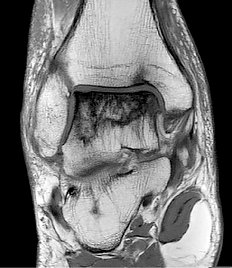

Das MRT wird in der modernen Medizin immer wichtiger, da diese Bildgebung ohne Röntgenstrahlen auskommt und eine sehr gute Option ist, weichteildichte Strukturen mit gutem Kontrast darzustellen. Es muss hier wesentlich unterschieden werden bezüglich der Feldstärke. Während die meisten Systeme heutzutage immer noch 1.5 T basiert sind und niedrigere Feldstärken aufgrund der dann schlechteren Bildqualität immer mehr im Alltag verschwinden, wird in unserer Abteilung zusätzlich das modernste 3 Tesla- MRT-Gerät in Thüringen betrieben. Besonders vorteilhaft ist dieses Gerät in der Beurteilung des Oberbauchs über eine spezielle Technik, die auch die Untersuchungsdauer verkürzt (sog. M-Dixon), aber auch die Beurteilung des Hirns, der Gelenke sowie der Vorsteherdrüse ist qualitativ durch kein anderes Gerät erreichbar. Andere Bildgebungen sind mit 3 Tesla vergleichbar zum ebenfalls auf modernstem Niveau befindlichen 1,5 T System. Im Bereich MRT haben wir in Nord- und Westthüringen in zahlreichen Bereichen besondere Behandlungsschwerpunkte und bieten Untersuchungen an, die sonst weder ambulant noch stationär angeboten werden. Dazu gehört das Prostata-MRT, die Analyse der stofflichen Zusammensetzungen eines Befundes im Kopf über die sog. Spektroskopie, die Darstellung der Nervenbahnen über die sog. Diffusionstensorbildgebung im Hirn, die Erstellung von Ganzkörperaufnahmen in nur 3mm Schichtdicke. Aber auch das Herz-MRT ist durch uns zertifziert hochqualifiziert möglich. Nach aktuellem Stand (5/2013) führt die Radiologieabteilung des Südharzklinikums in Deutschland unter allen Radiologien die achtmeisten registrierten und zertifizierten Herz-MRT durch, nach der Universität Jena die meisten Mamma-MRT in Thüringen. Wir sind europäisches Referenzzentrum für Ganzkörper-MRT und Prostata-MRT und haben über zahlreiche MR-Themen in unterschiedlichen Kongressen publiziert. Die MR-defäkographie kann bei Beckenbodenproblemen sehr hilfreich sein und wird bei uns seit Jahren erfolgreich angewandt. Unser Untersuchungskonzept wurde hier von der Europäischen Röntgengesellschaft als Veröffentlichung für die Ausbildung von Radiologen in ganz Europa angenommen.